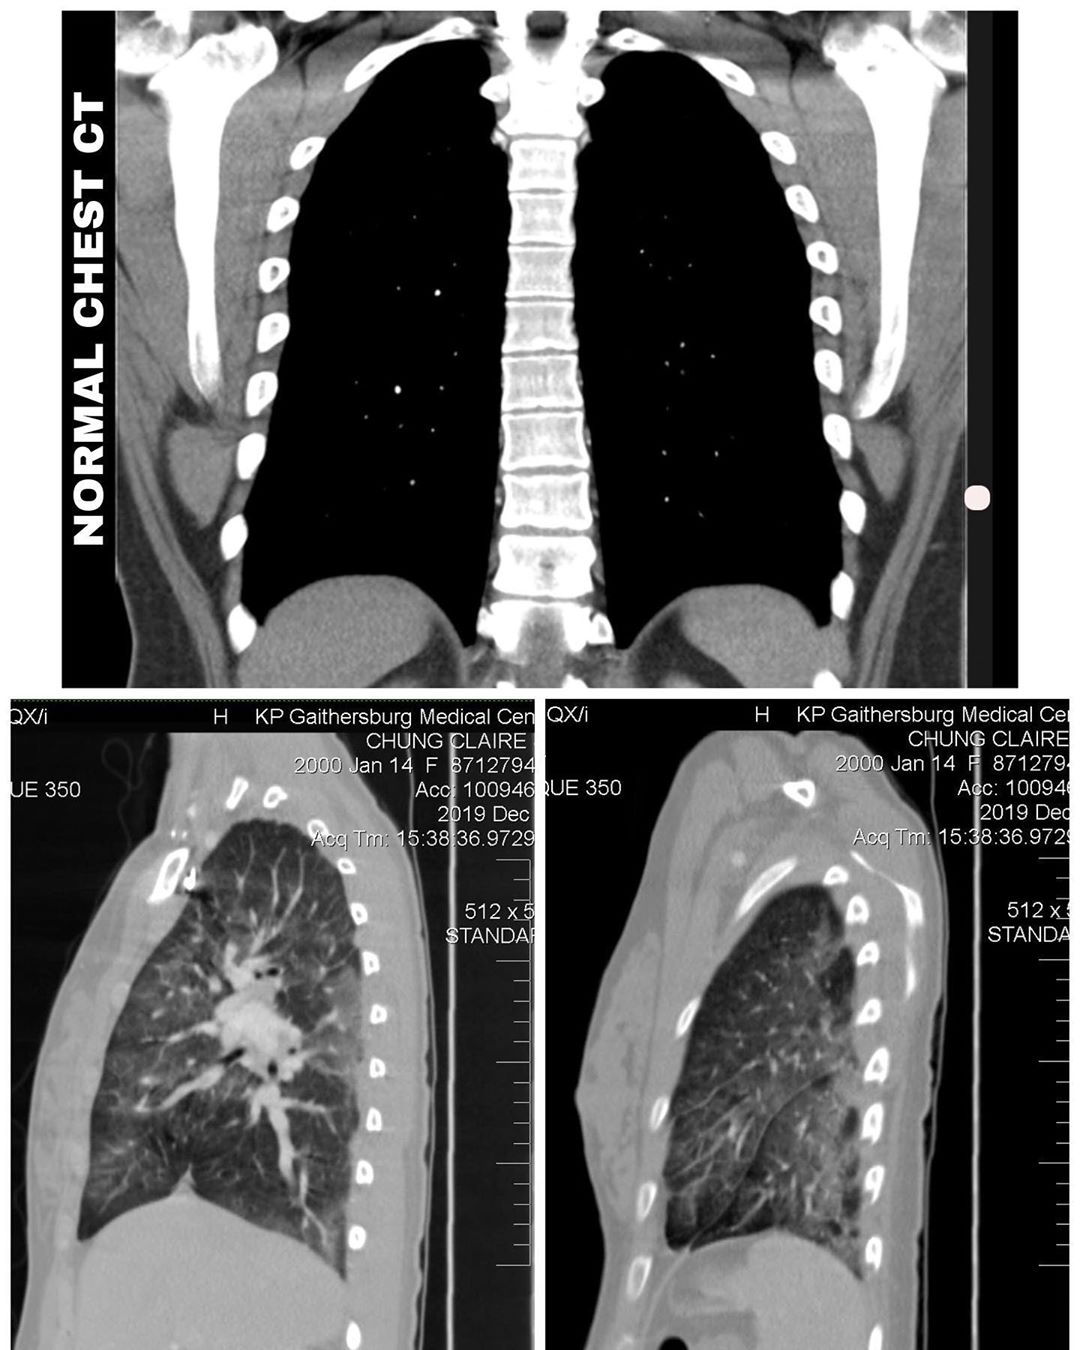

Claire 之后在 Instagram 上传她的电脑断层扫描结果,从这些X光片中可以看到,正常的肺是黑的,但她的肺已经变成是一片混浊而且发白的。

▼ 图 ②(上图为正常的肺,下图为 Claire 的检查结果。)